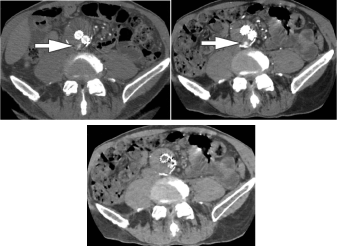

DECT helps in differentiating excretory organ calculi by analysis of underlying composition, as uric acid stones are composed of lighter components (hydrogen, carbon, oxygen, and nitrogen) whereas non-uric acid stones are composed of heavier components (calcium, phosphorus, and sulfur) [5,18,19] (Figure 1).

Figure 1. DECT characterization of excretory organ stones. A. DECT axial image shows left excretory organ calculus (stone) with attenuation of 825 HU at one hundred forty kVp. B. This image has 1250 HU attenuation at eighty kVp. C. The stone was firm to be composed of calcium oxalate monohydrate victimization DECT post process algorithms. Reprinted with permission from Coursey CA, Nelson RC, Boll DT, et al. Dual-energy multidetector CT. Radiographic. 2010;30(4): 1045.Uric acids stones demonstrate exaggerated photons attenuation at a hundred and forty kVp as a result of the attenuation is driven primarily by Compton scatter (due to lighter 30% chemical composition).

Conversely, non-uric acid stones demonstrate exaggerated attenuation at eighty kVp because Uric acids stones demonstrate exaggerated photons attenuation at a hundred and forty kVp as a result of the attenuation is driven primarily by Compton scatter (due to lighter 30% chemical composition). Conversely, non-uric acid stones demonstrate exaggerated attenuation at eighty kVp because of exaggerated electricity impact contribution from the heavier parts nearing the K-edge of the metallic element (Z=20). victimization the two-material (basis pair) decomposition approach on DECT, water and iodine image datasets square measure generated. Stone look on water image solely suggests acid calculi, whereas look on every water and iodine image indicate non-uric acid stones (Figure 2). Effective Z (Zeff) pictures square measure AN alternate approach for characterizing internal organ calculi and should be achieved in the offline computing device. Zeff weighs each the attenuation and number of bound materials, thereby serving to in characteristic the materials that are predominant among mixed stones.

Figure 2. 45-year-old man (top row) and 60-year-old man (bottom row) with renal lithiasis. typical true unenhanced image (A), water material decomposition image (B), and iodine material decomposition image (C) demonstrate a non-uric acid stone, that's hyperdense on every water and iodine pictures (arrows) in single offer DECT (GE). at intervals, the second patient, typical true unenhanced image (D), water image (E), and iodine image (F) demonstrate a mixed stone that is predominantly acid in composition (arrows). The stone is not hyperdense on iodine pictures aside from its peripheral rim (F). Our experience has shown that acid stones typically demonstrate a rim of Ca deposition.